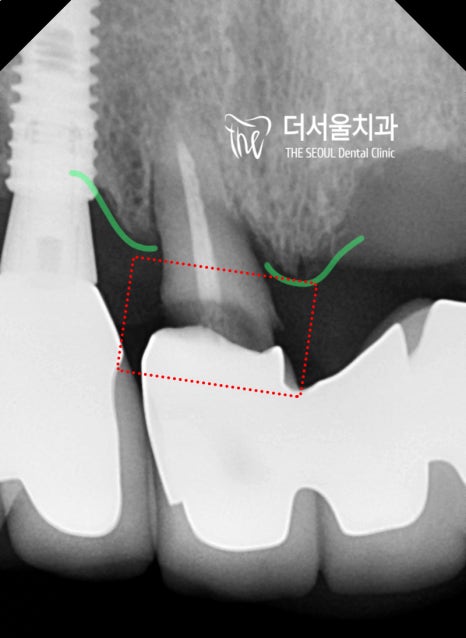

먼저 포지션을 설정하며

식립 기울기 및 보철의 형태를 예측합니다.

이어서, 뼈의 단면 및 골질을 파악하며

최선의 결과를 낼 수 있는 위치를 찾는거죠.

표시를 해 둔 곳을 보면

심겨질 implant fixture 의 직경과,

뼈의 두께가 거의 비슷한 것을 볼 수 있죠?

따라서 치조골 이식술 이라 해서

뼈 이식을 하기로 했습니다.